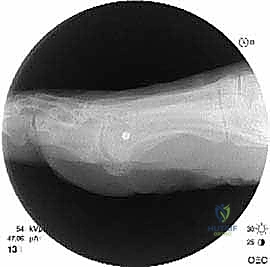

* الأشعة السينية العادية (X-rays) أثناء الوقوف: هذا هو الفحص الأهم. يتم أخذ صور للقدمين أثناء تحمل الوزن لقياس زوايا العظام بدقة، وتحديد مقدار النقص في طول مشط القدم الأول مقارنة بالثاني (يجب أن يكونا متقاربين في الطول ضمن نسب محددة).

* التصوير المقطعي المحوسب (CT Scan): يُطلب في الحالات المعقدة لتقييم جودة العظم المتبقي والتخطيط الدقيق للقص الجراحي ثلاثي الأبعاد.

* الرنين المغناطيسي (MRI): لتقييم الأنسجة الرخوة، مثل تمزق الأربطة الأخمصية أو تلف الغضاريف في المفاصل.